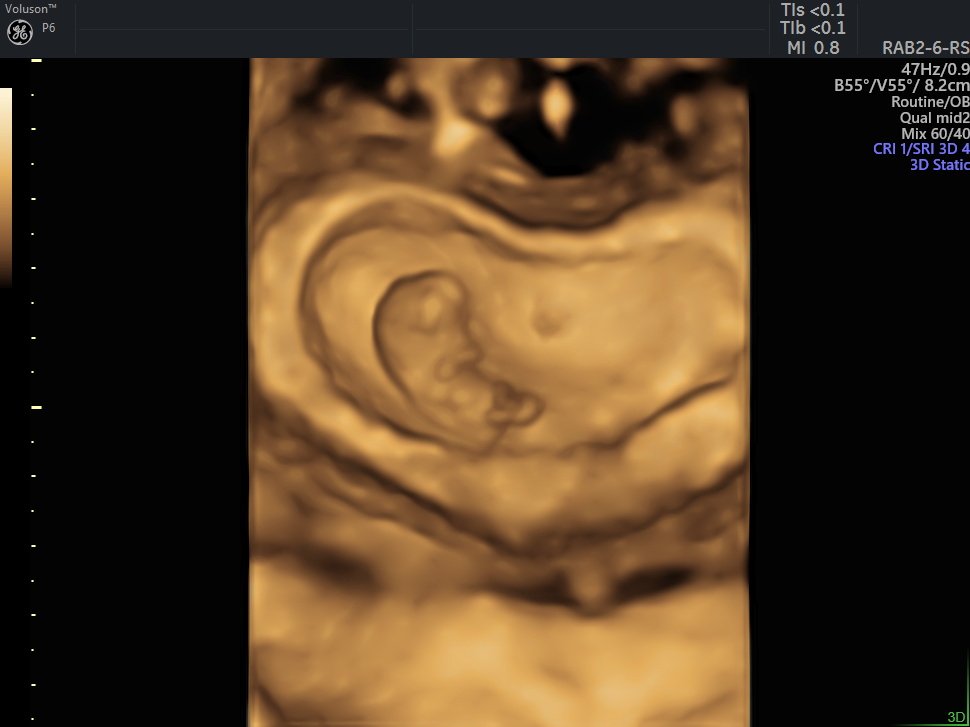

4 Boyutlu (Renkli) Ultrason ve Doppler Ultrasonografi

4 D Ultrasonografi